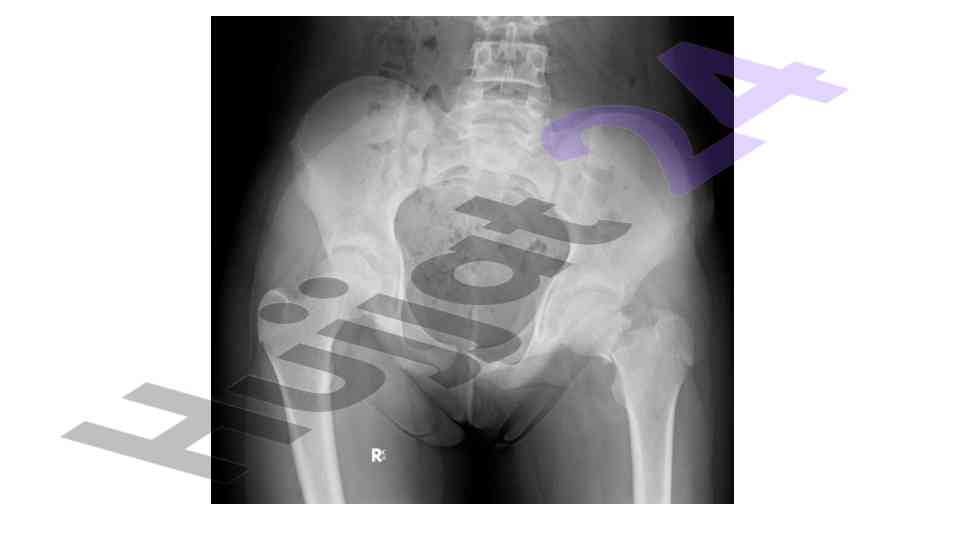

An overview of the muskuloskeletal system with a focus on pediatric applications and implications for treatment.